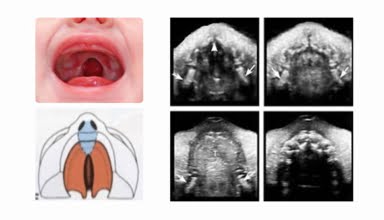

[Video] Siêu âm khảo sát bất thường vùng mặt thai nhi, Bs Loan

Siêu âm khảo sát bất thường vùng mặt thai nhi là bài giảng trong Khóa học Siêu âm Sản phụ khoa (BV Từ Dũ) do ThS Ngô Thị Kim Loan giảng dạy.